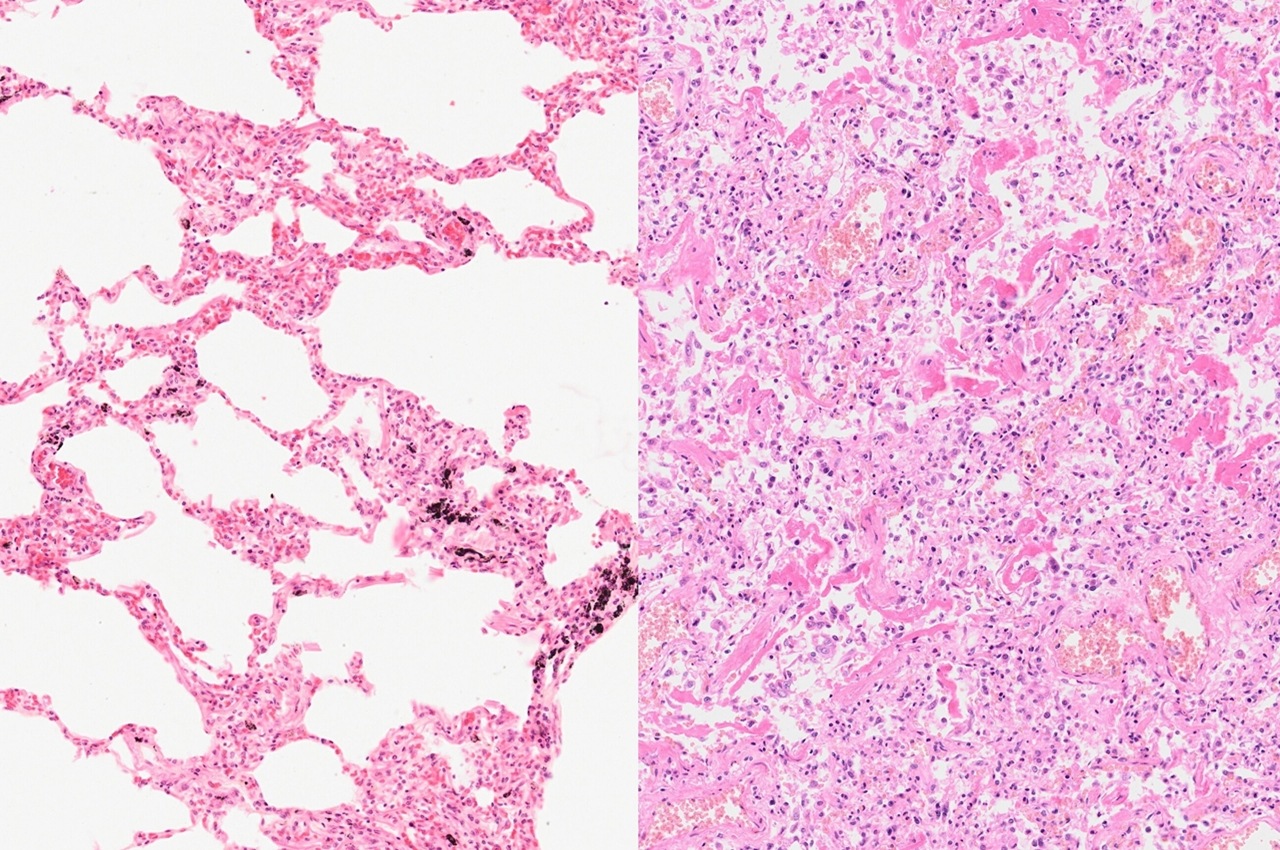

Normálne, nepoškodené pľúca sú vzdušné, ľahké, na pohmat mäkké. V alveolách, drobných dutinkách, ktoré tkanivo pľúc tvoria, sa za bežných okolností vyskytuje vzduch. Počas ARDS dochádza k pomerne rýchlemu a drastickému vyplneniu týchto dutiniek najskôr tekutinou, následne bielkovinovým materiálom, imunitnými bunkami a nakoniec v časti prípadov až väzivom.

Hmotnosť takýchto pľúc sa zvyšuje často až na päťnásobok bežných hodnôt, pľúca sa stanú tuhými, nevzdušnými. V takomto stave pľúca nie sú schopné správne vymieňať dýchacie plyny a pacient sa jednoducho zadusí.